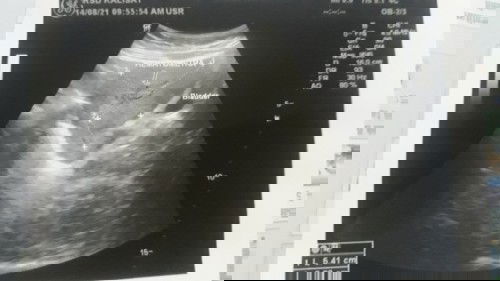

Sedikin cerita bun.saya kemaren waktu hamil 21 week 6 day.janin saya tidak bergerak selama satu hari.saya periksa kebidan detak jantungnya masih ada tapi lemah(110)dan dokter menyarankan USG.dan keesokan harinya saya USG.dan detak jantung bayi saya sudah berhenti.dan harus segera dikeluarkan melalui proses induksi. Di kehamilan sebelumnya saya juga mengalami hal yg sama(Abortus).kira2 apa penyebabnya bun?soalnya saya takut terjadi lagi.saya nanyak ke dokter.dokternya jawab kurang tauđ„ #seriusnanya